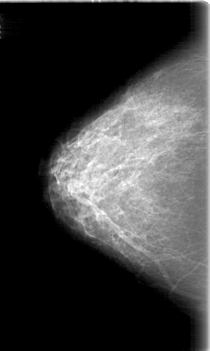

D_4058_1.RIGHT_MLO

RIGHT_CC LINES 5251 PIXELS_PER_LINE 3136 BITS_PER_PIXEL 12 RESOLUTION 43.5 NON_OVERLAY